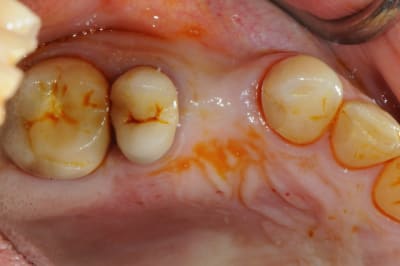

pour débuter ce post je propose un petit cas avec une ROG un comblement alvéolaire et un lambeau pédiculé pour fermer le site d'extraction.

un petit exemple de ce matin: extraction des piliers 12 et 14, curetage, comblement avec du bio-oss de la dépression osseuse vestibulaire au niveau de l'inter 13, comblement des alvéoles 12 et 14 au genos et recouvrement par 2 pédicules conjonctifs. Temporisation avec un partiel amovible.